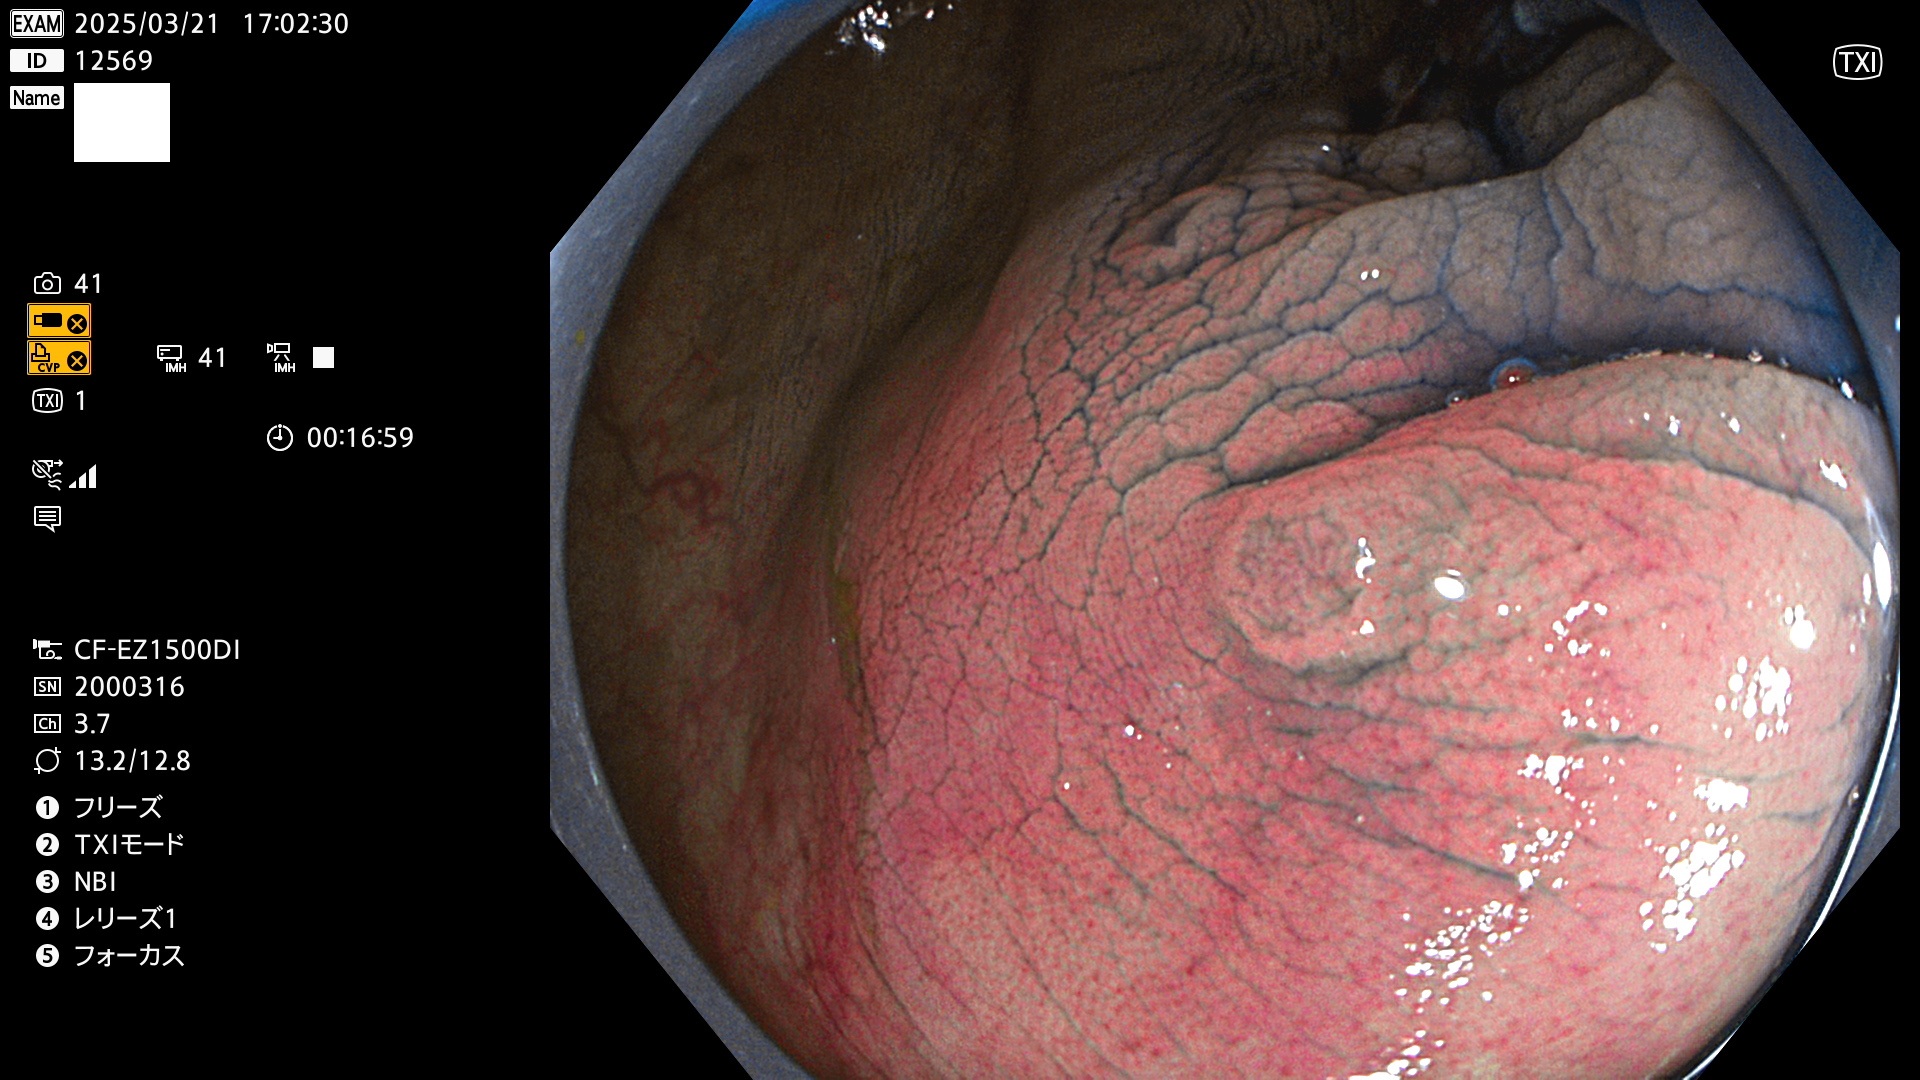

今週のUb、Uc型腺腫

完全に平坦な物をUb、陥凹している物をUcと呼びます。Ubは認識が困難で、Ucはびらん(炎症)と紛らわしいために見落とされやすく、「内視鏡後・大腸癌」の原因になります。

毎週の検査(木・金・土・日)に発見されたUb、Uc型・腺腫を、その週の日曜の夜にUPし1週間、提示します。

抽出の対象期間 2025年3月20日〜3月23日の4日間(48件の検査)10個 (10/48=21%)